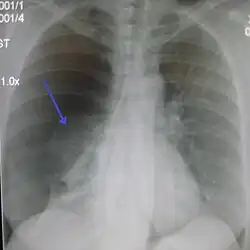

Chest X-ray

A plain chest radiograph, ideally with the X-ray beams being projected from the back (posteroanterior, or "PA"), and during maximal inspiration (holding one's breath), is the most appropriate first investigation.[35] It is not believed that routinely taking images during expiration would confer any benefit.[36] Still, they may be useful in the detection of a pneumothorax when clinical suspicion is high but yet an inspiratory radiograph appears normal.[37] Also, if the PA X-ray does not show a pneumothorax but there is a strong suspicion of one, lateral X-rays (with beams projecting from the side) may be performed, but this is not routine practice.[18][22]

Chest X-ray showing a pneumothorax on the right (left in the image), where the absence of lung markings indicates that there is free air inside the chest -

Chest X-ray showing the features of pneumothorax on the left side of the person (right in image)

It is not unusual for the mediastinum (the structure between the lungs that contains the heart, great blood vessels, and large airways) to be shifted away from the affected lung due to the pressure differences. This is not equivalent to a tension pneumothorax, which is determined mainly by the constellation of symptoms, hypoxia, and shock.[16]

The size of the pneumothorax (i.e. the volume of air in the pleural space) can be determined with a reasonable degree of accuracy by measuring the distance between the chest wall and the lung. This is relevant to treatment, as smaller pneumothoraces may be managed differently. An air rim of 2 cm means that the pneumothorax occupies about 50% of the hemithorax.[18] British professional guidelines have traditionally stated that the measurement should be performed at the level of the hilum (where blood vessels and airways enter the lung) with 2 cm as the cutoff,[18] while American guidelines state that the measurement should be done at the apex (top) of the lung with 3 cm differentiating between a "small" and a "large" pneumothorax.[38] The latter method may overestimate the size of a pneumothorax if it is located mainly at the apex, which is a common occurrence.[18] The various methods correlate poorly but are the best easily available ways of estimating pneumothorax size.[18][22] CT scanning (see below) can provide a more accurate determination of the size of the pneumothorax, but its routine use in this setting is not recommended.[38]

Not all pneumothoraces are uniform; some only form a pocket of air in a particular place in the chest.[18] Small amounts of fluid may be noted on the chest X-ray (hydropneumothorax); this may be blood (hemopneumothorax).[16] In some cases, the only significant abnormality may be the "deep sulcus sign", in which the normally small space between the chest wall and the diaphragm appears enlarged due to the abnormal presence of fluid.[19]